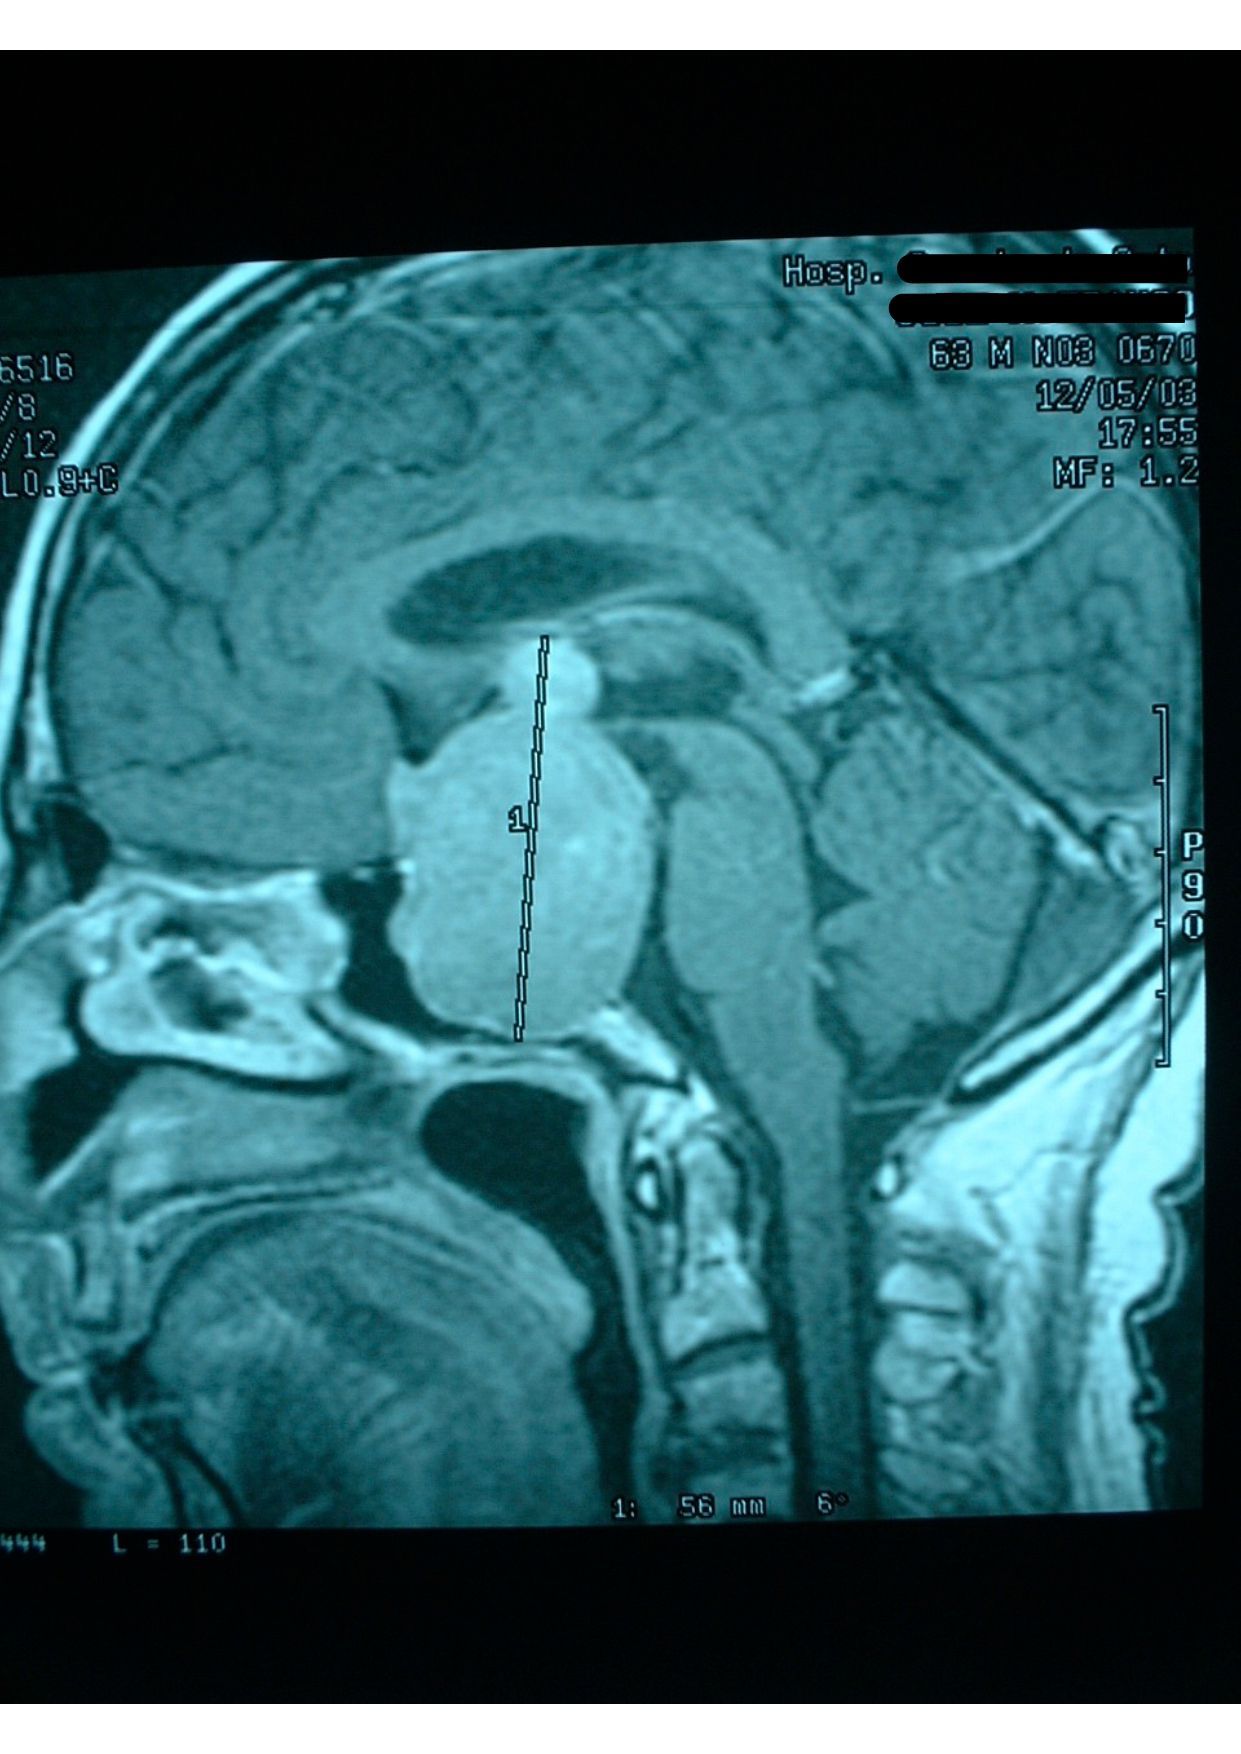

Tumores da Hipófise

- Diagnóstico e tratamento especializado de tumores nesta glândula essencial.